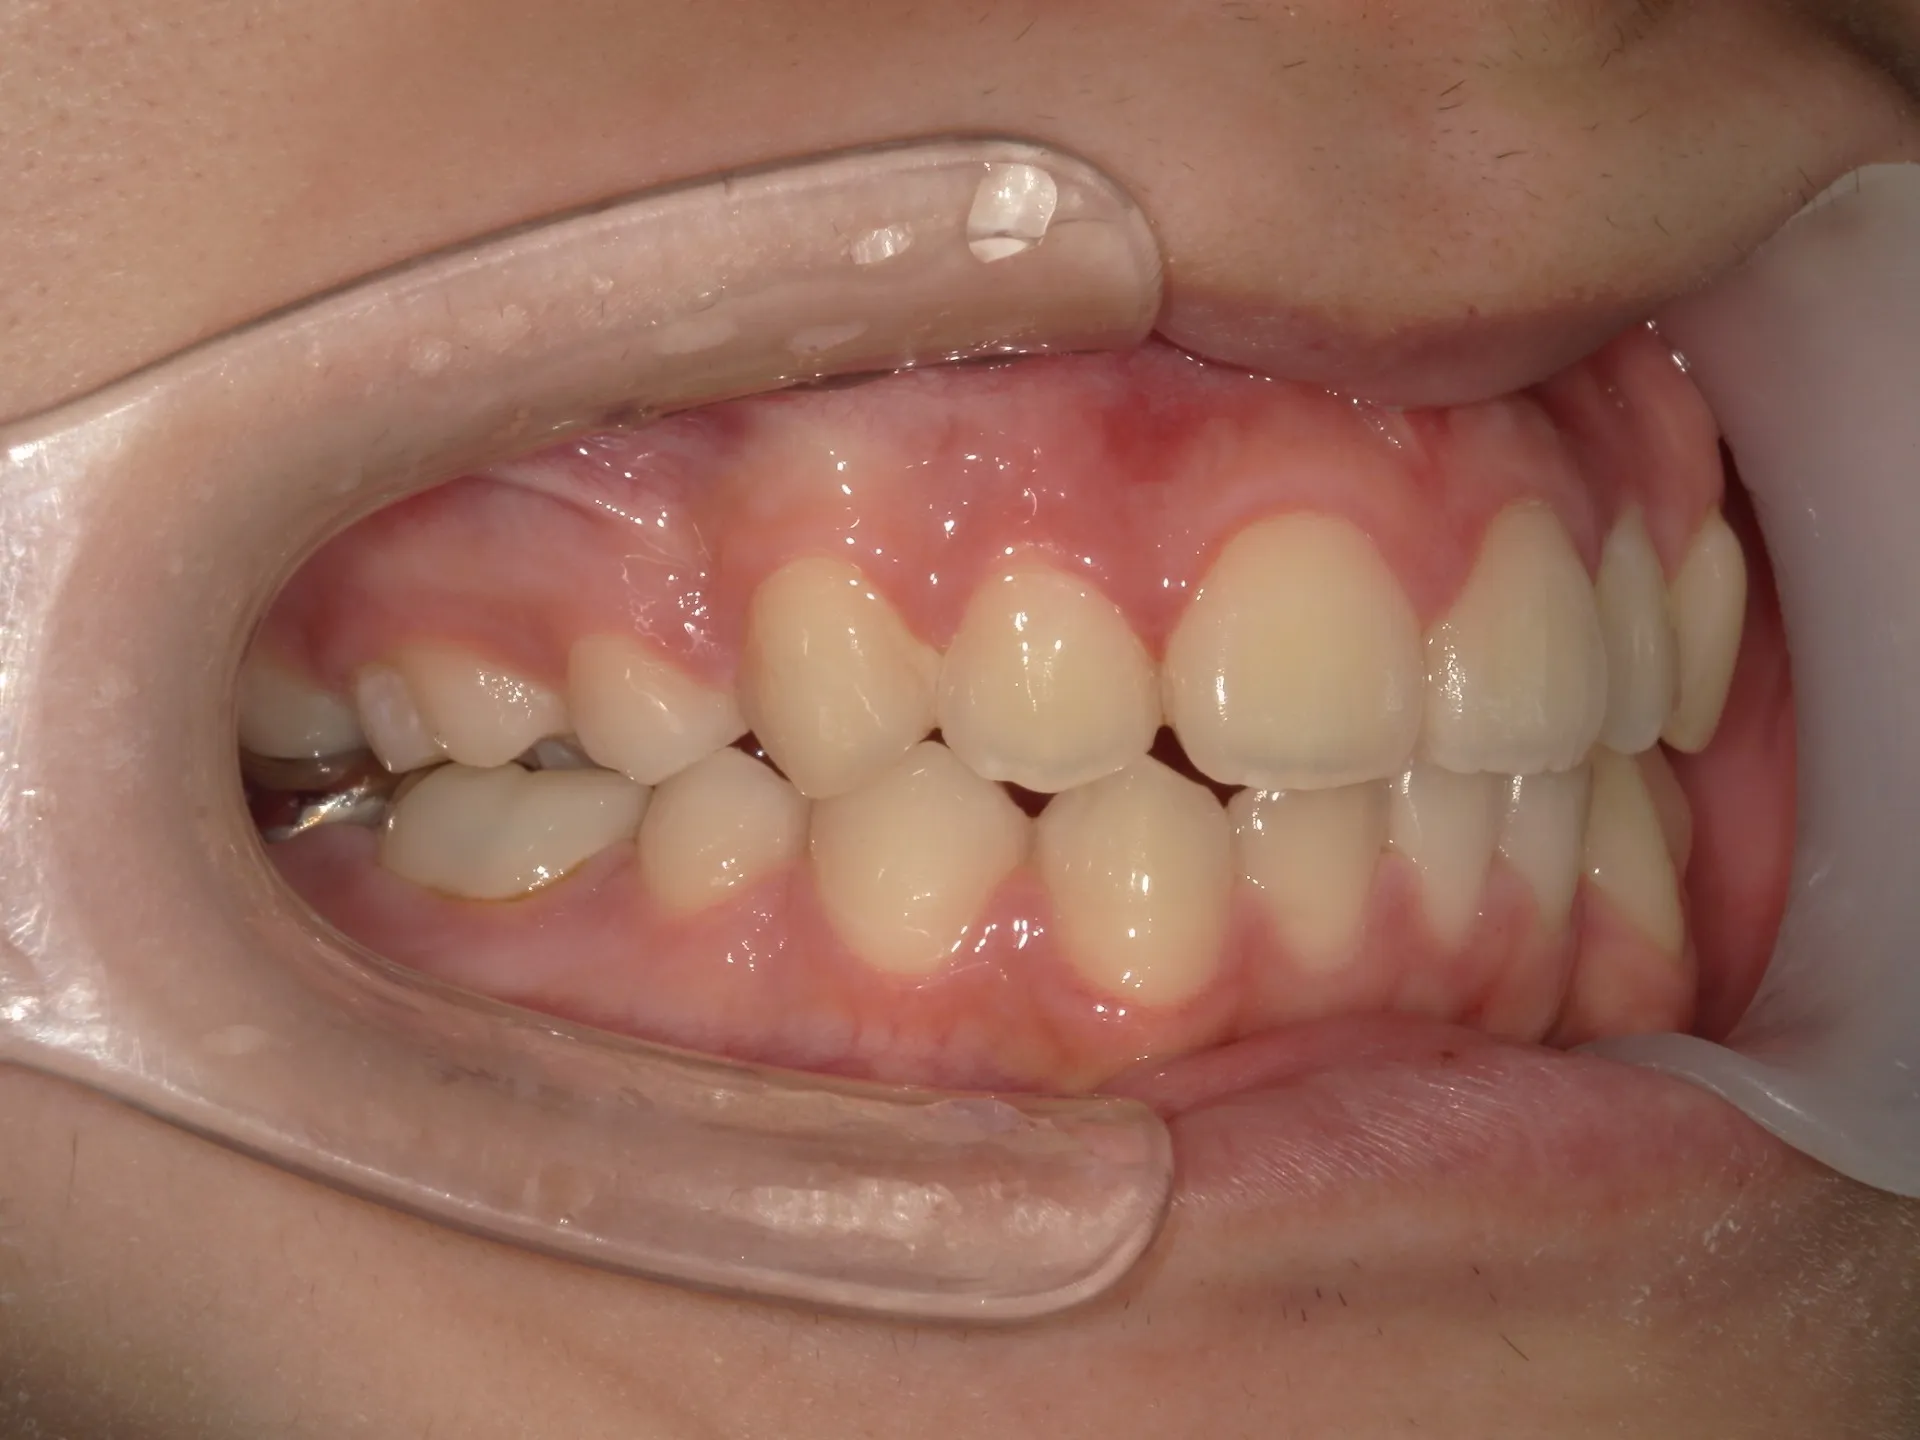

今回は下の前歯が1本ない場合の矯正治療についてご紹介いたします。